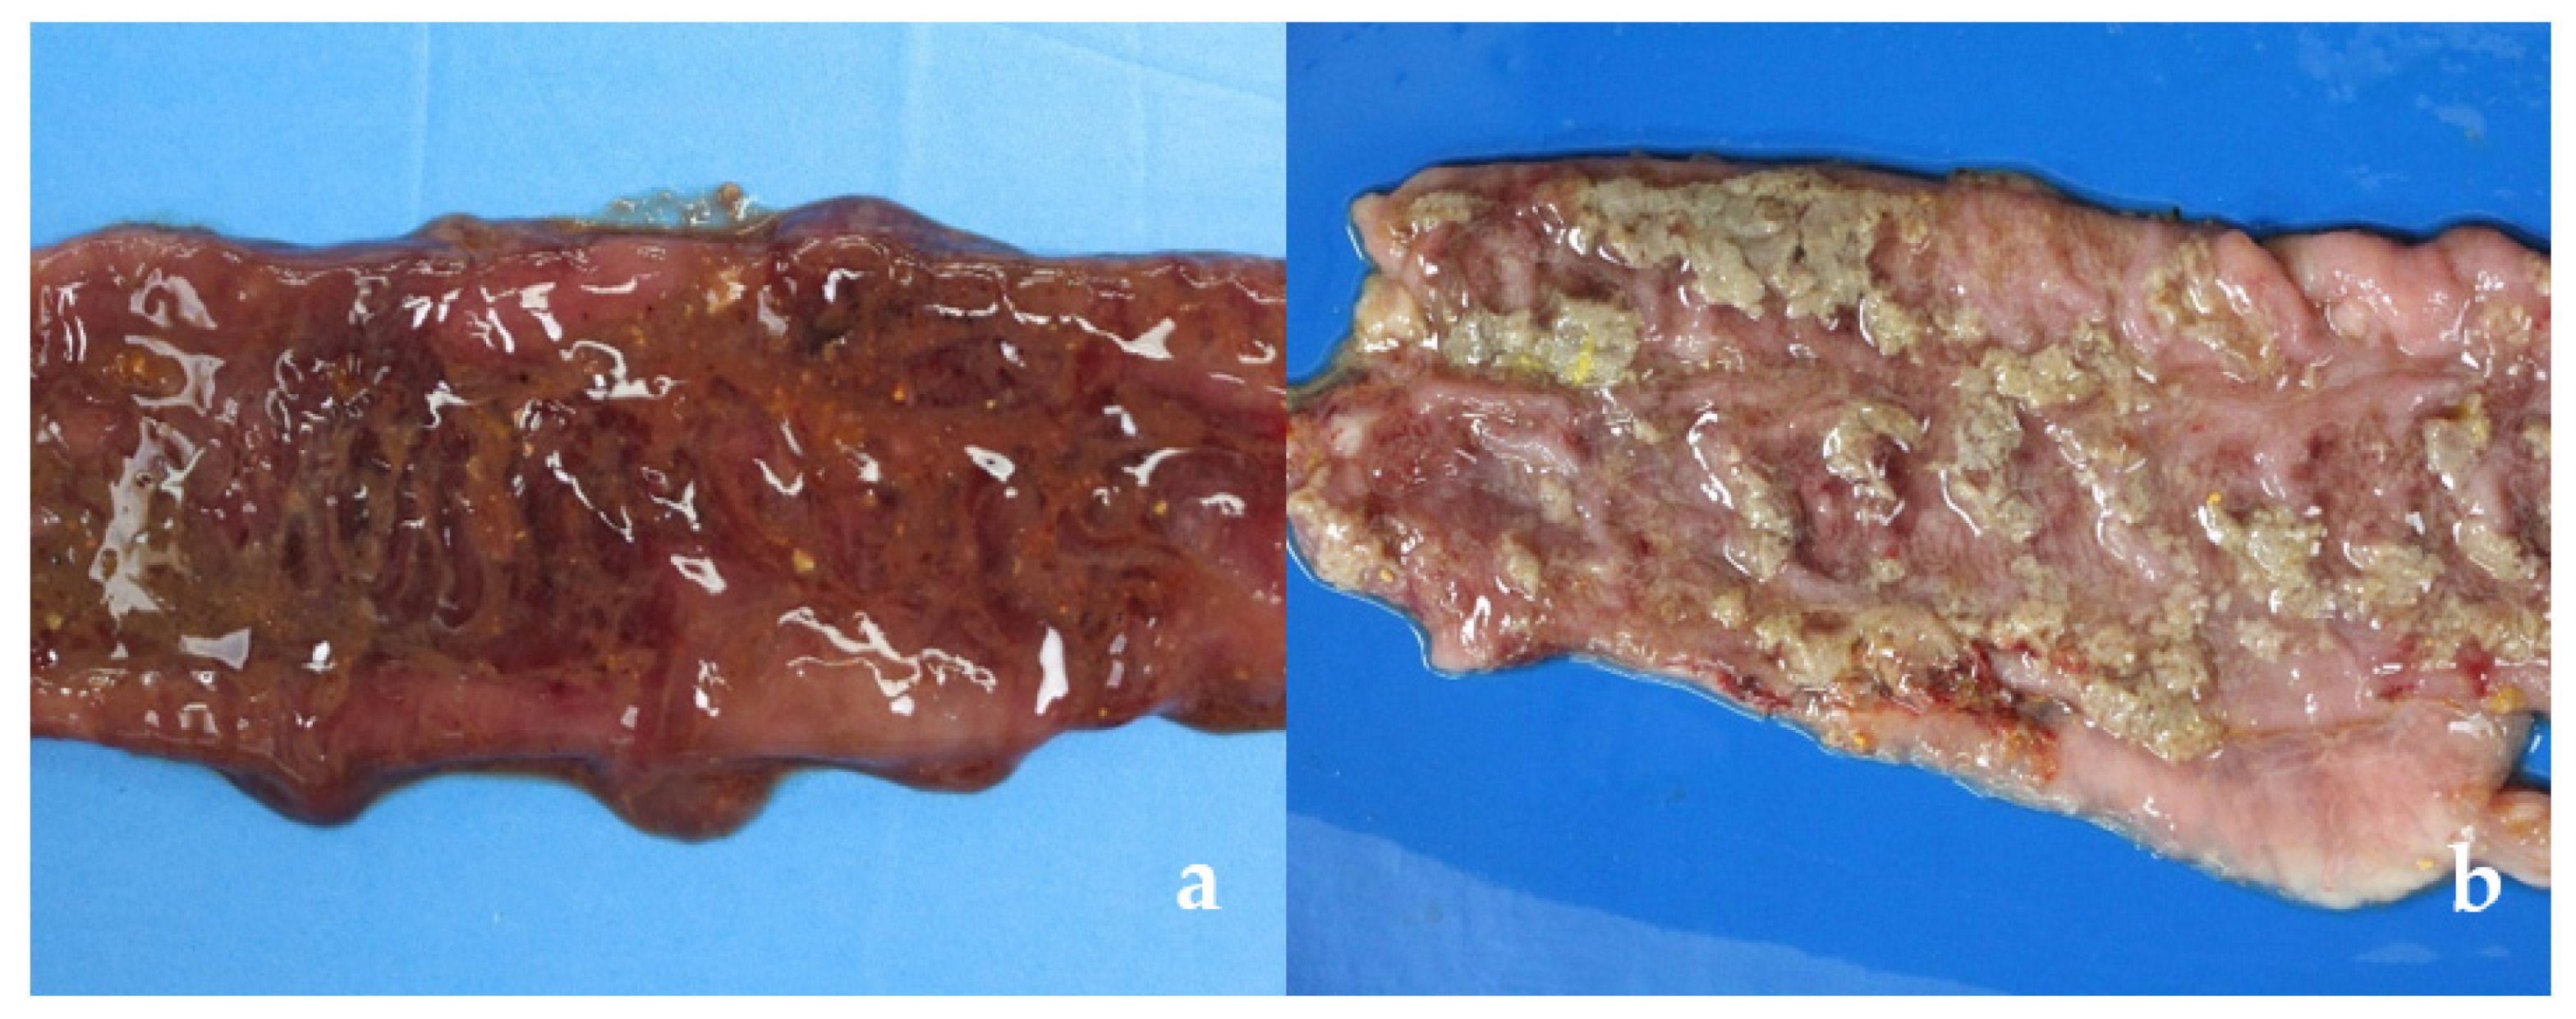

3.2.1. Gross Lesions